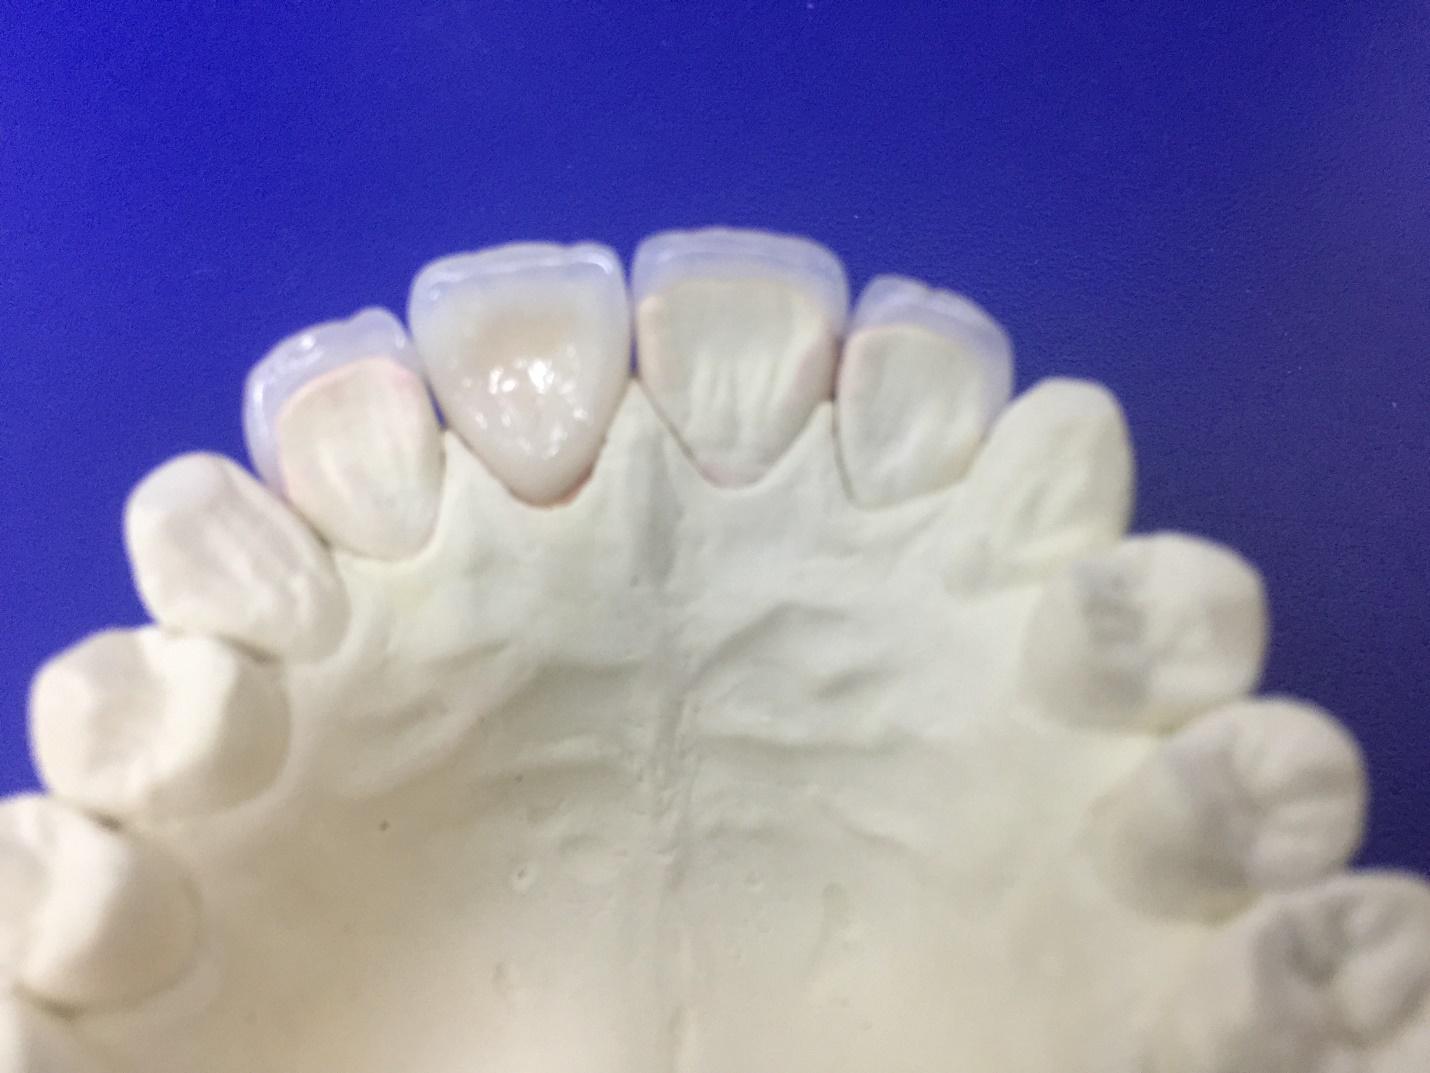

Ниже представлены фото аппарата и примеры работ: